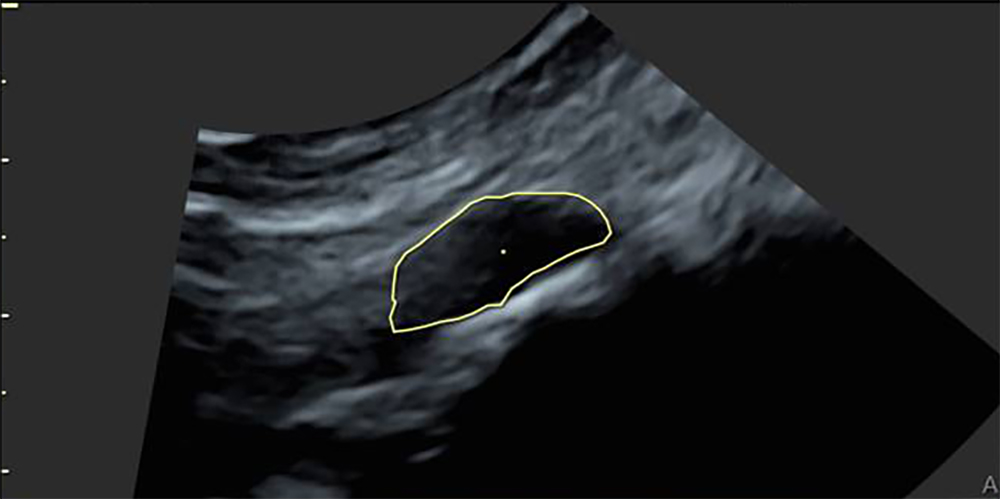

In January 2021 a check-up mammogram revealed several benign cysts in both my breasts. When I looked at the ultrasound images, I noticed how those cysts were the most prominent presence in the image; they looked like black holes in the faint, grey, oval shape of my crushed breast. At the top left-hand side of the image I read the word ‘Mamma’.

'Mastopathy with multiple smaller cysts and mastopathic microcalcifications.

No suspicious features. BI-RADS classification 2.'

• Production process

3D ultrasound pictures of breast tissue; volume of cysts traced using special software; exported as 3D model, 3D printed, sanded and polished, cast in silver.